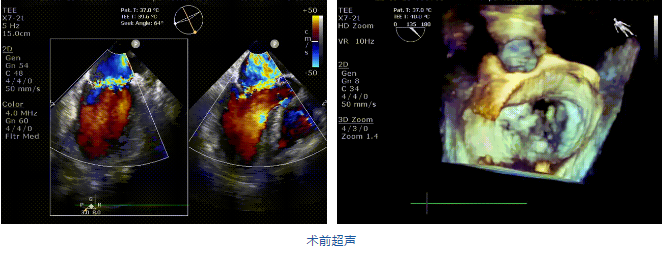

接受治療的是一例二尖瓣重度反流的患者,主訴“突發(fā)間歇性胸悶,氣急6天”。術前超聲提示:1.二尖瓣脫垂伴重度關閉不全(瞬時量30ml);2.左心、右房增大(左房容積110ml,左室容積129ml,右房容積55ml);3.左室收縮功能正常?;颊咴诔浞謽藴驶幬镏委熀螅℅DMT)仍然癥狀明顯,韓林教授及其團隊唐楊烽教授,以及心超科的周廣為醫(yī)生決定使用我國創(chuàng)新器械JensClip為患者進行二尖瓣緣對緣修復手術。

在阜外醫(yī)院潘湘斌教授團隊的支持下,手術經股靜脈-房間隔入路,采用全身麻醉插管,在TEE和DSA引導下完成房間隔穿刺。置入JensClip瓣膜夾系統(tǒng)后,在左房調整瓣膜夾的位置和軸向,后進入左室,在TEE引導下捕捉二尖瓣前后瓣葉,并關閉瓣膜夾。經TEE反復確認手術效果后最終鎖定并釋放瓣膜夾。術后即刻超聲顯示瓣膜夾位置穩(wěn)定,功能良好,二尖瓣反流由術前4+減少至微量,手術圓滿成功。